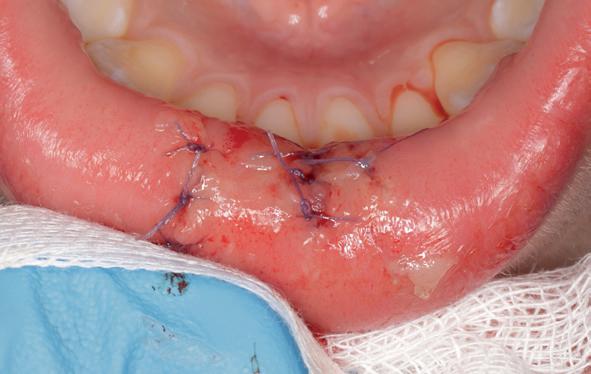

Behandeling 42, 41, 31

Na het verwijderen van de lekkende glasionomeerspalk, lagen alle pulpae bloot. De 42 was bovendien verticaal gefractureerd (afbeelding 12 en 13). Het topje van de pulpae van de 31 en 41 kon worden verwijderd, en na spoelen met NaOCl persisteerden twee vitale pulpae, die zijn afgedekt met een laagje Vitrebond (afbeelding 14).

Daarna zijn de tanden weer opgebouwd met een composietrestauratie van Filtek Z250 kleur A3. De 42 is tijdelijk afgesloten met glasionomeercement, met het verzoek aan de tandarts deze tand te extraheren.